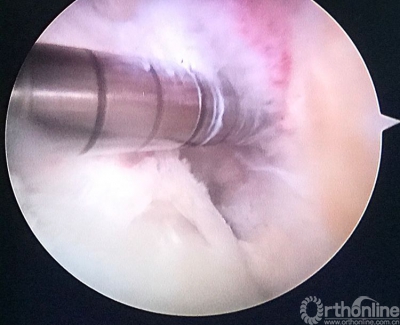

现等离子刀头所指处应该为正确的内口定位,原内口与此处相距较远。

股骨隧道内口先用克氏针定位,调整角度尽量避开原过于偏后的隧道。

用由小到大的空心钻头钻股骨隧道,观察隧道情况,至8mm时隧道内骨面90%达新鲜化。